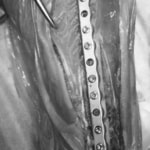

当院ではAdvanced Locking plate system(ALPS)と、Locking compression plate system(LCPS)という骨接合法で骨折症例の治療を行っています。

LCPは、スクリュー(ネジ)とプレート(金属の板)をロックする特殊な構造により骨折部位を固定する新しい世代のプレートシステムです。ひとつのホールでロッキングスクリューとスタンダードスクリューの使用を選択できるユニークな構造をしているため、骨折断端間の圧迫を目的とした従来型プレート固定法に加え、高い角度安定性を有するロッキングスクリューを用いた固定法の選択が可能です。従来のプレートシステムでは困難だった部分の骨折や癒合不全の症例に高い治療効果をもたらします。

Locking compression plate system の特徴

1.骨膜上の血行障害は最小限

2.高い角度安定性

3.プレート設置時の整復位喪失の防止

4.スクリューのルースニング(ゆるみ)の防止

5.コンビネーションホール

6.粗鬆骨における固定性の向上

7.1.5mmと薄いプレートのため、超小型犬にも使用しやすい

8.抜去が不要となることが多い